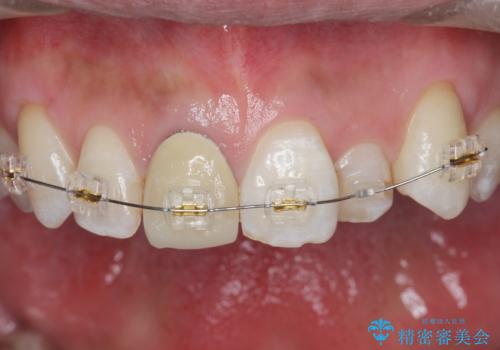

- 奥に引っ込んでいる前歯を矯正治療で並べたい!色の気になる前歯のクラウンをやり替えたい!と希望され来院されました。

奥に位置している前歯を部分ワイヤー矯正ののちマウスピース矯正インビザラインで並べ、矯正治療後に審美的なジルコニアクラウンを作製していきます。